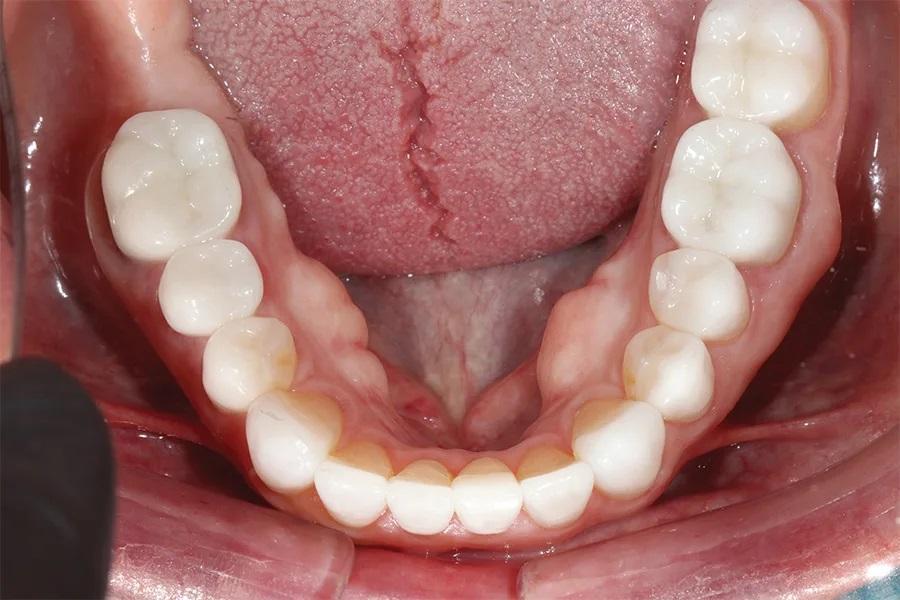

Фото 6. Окклюзионный вид нижней челюсти до лечения, демонстрирующий износ режущих краев и существующих металлокерамических коронок.

Биомеханический статус: Фарфор был истерт до металла на зубах 37 и 46. Временная конструкция на имплантате в области зуба 15 была сломана. Эрозивные поражения отмечались на зубах 13, 12, 23, 33 и 43. На зубе 17 имелась разрушенная амальгамовая пломба, а на зубе 35 — сомнительная реставрация (фото 6).